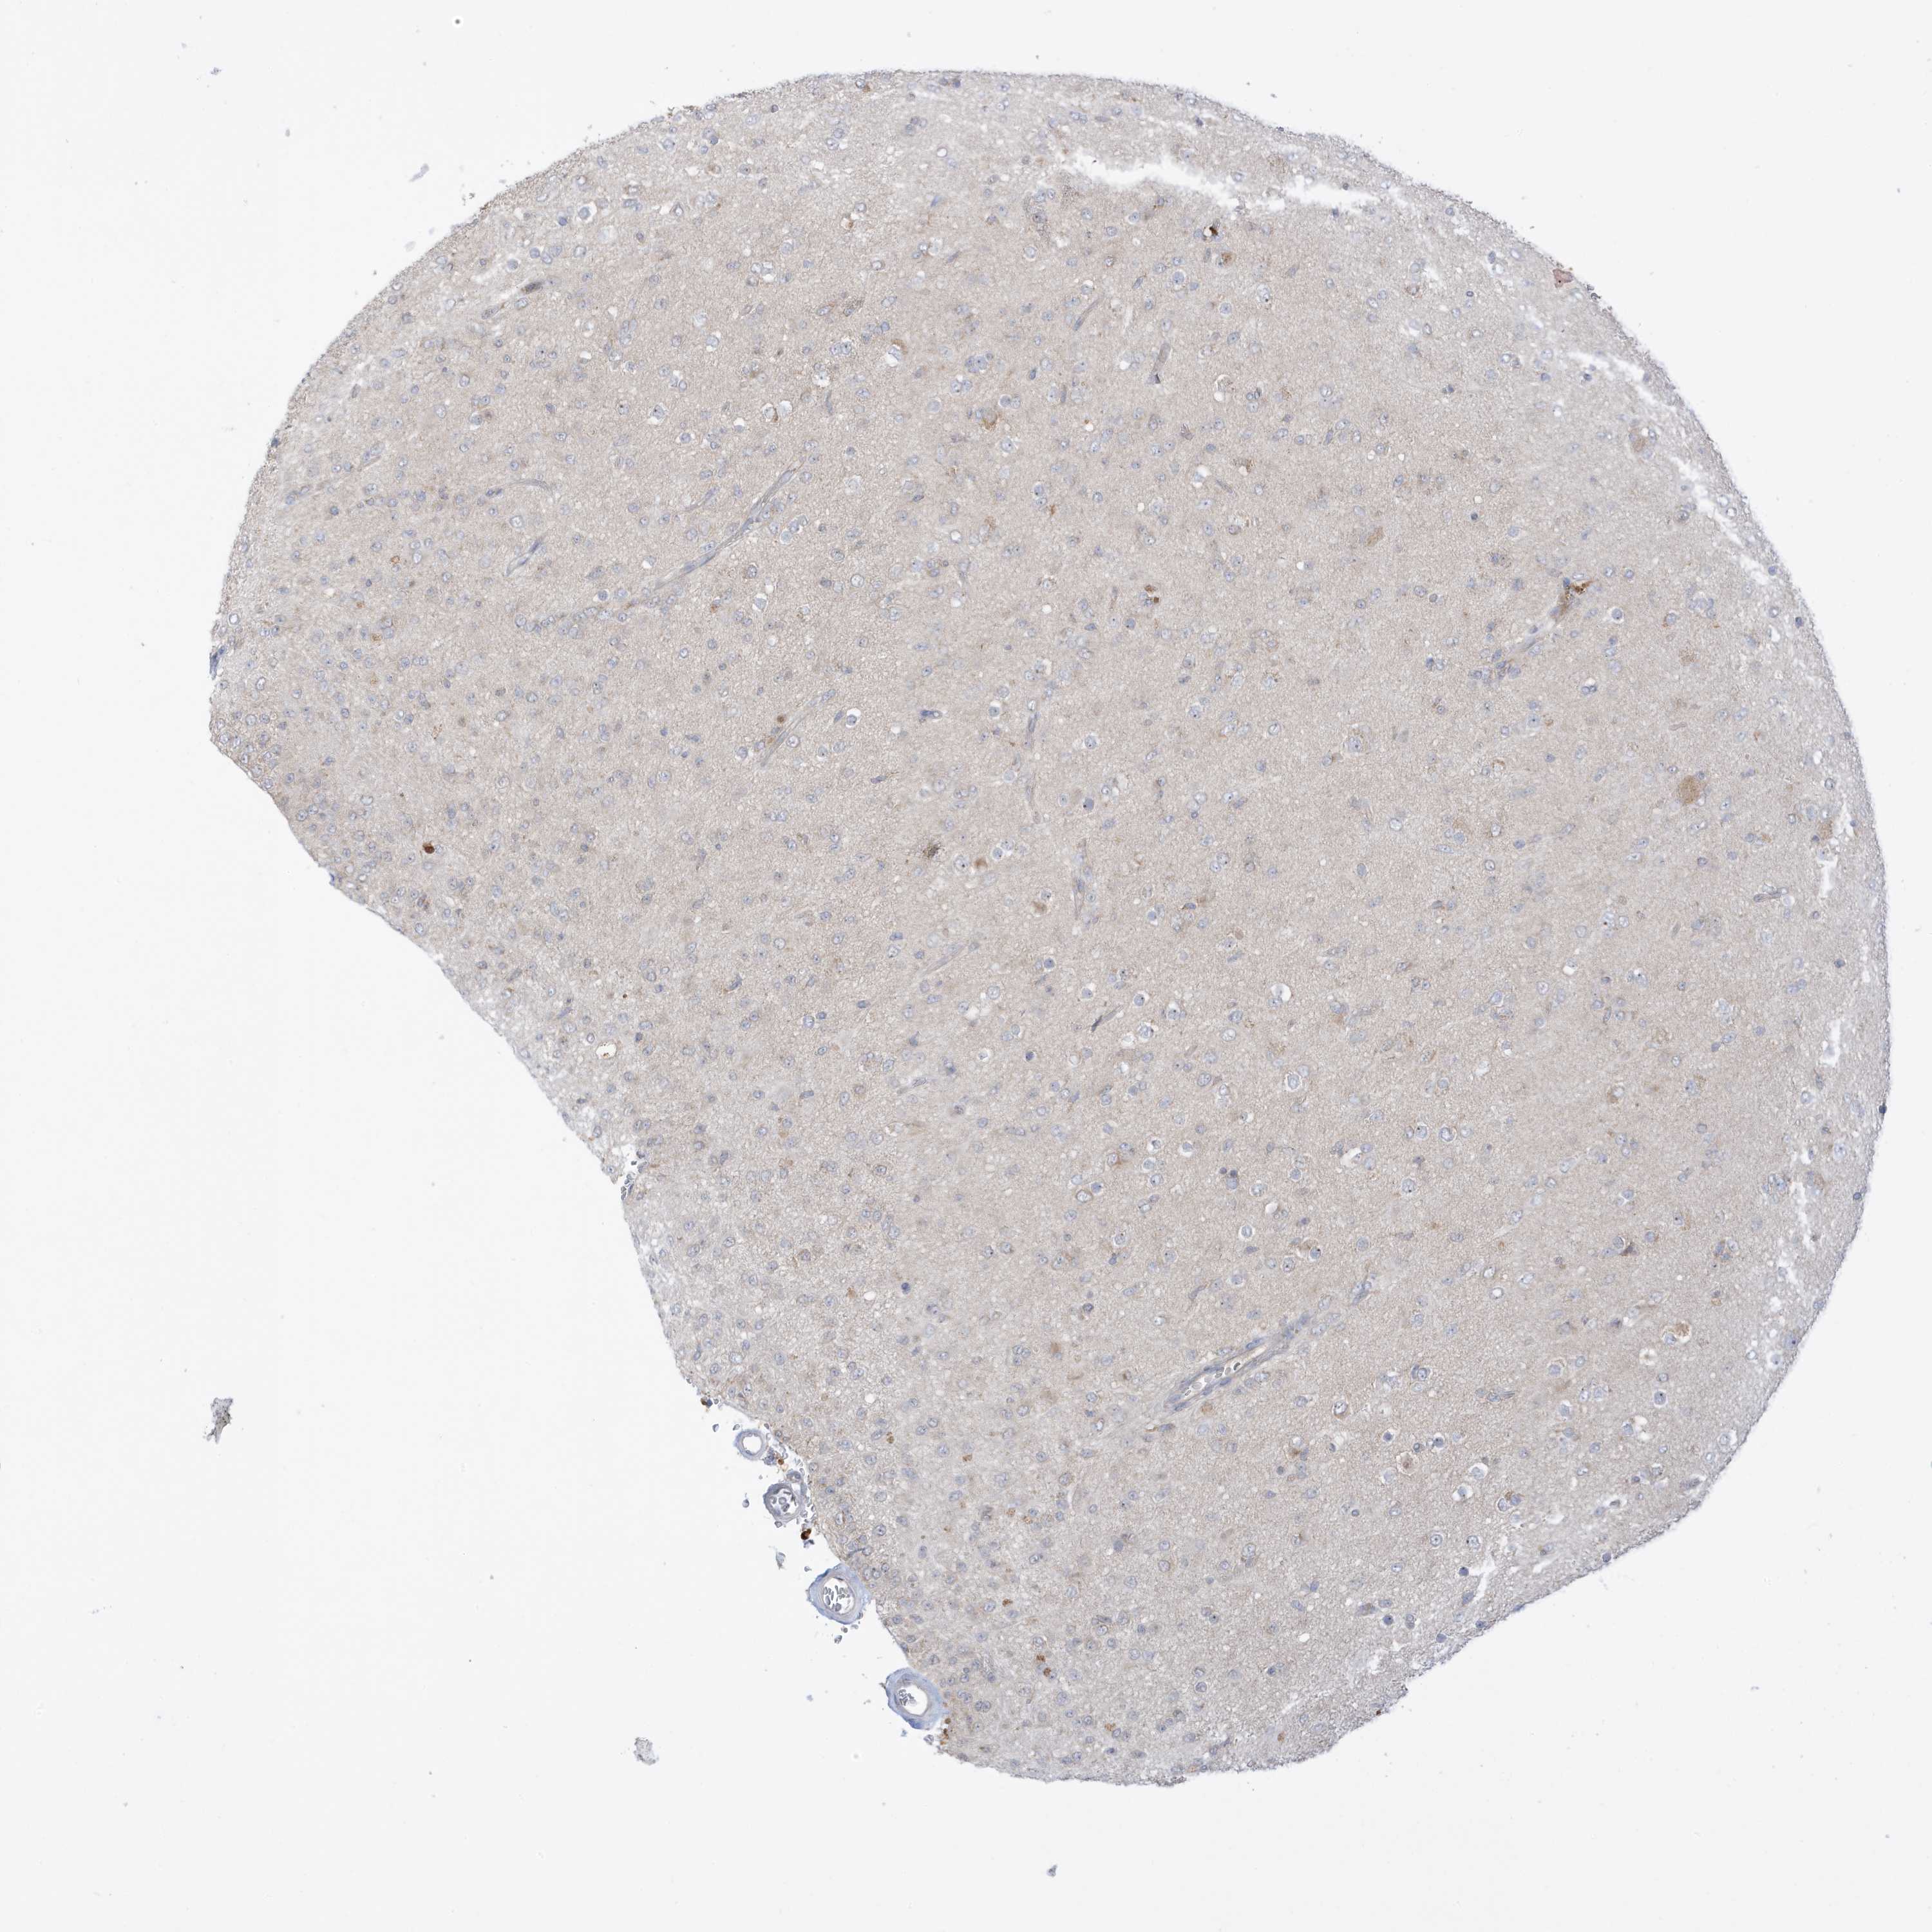

GLIOMA - Protein expressioni

A mouse-over function shows sample information and annotation data. Click on an image to view it in a full screen mode. Samples can be filtered based on level of antibody staining by selecting one or several of the following categories: high, medium, low and not detected. The assay and annotation is described here.

Note that samples used for immunohistochemistry by the Human Protein Atlas do not correspond to samples in the TCGA dataset.

Antibody stainingi

Antibody staining in the annotated cell types in the current human tissue is reported as not detected, low, medium, or high, based on conventional immunohistochemistry profiling in selected tissues. This score is based on the combination of the staining intensity and fraction of stained cells.

Each image is clickable and will lead to virtual microscopy that enables deeper exploration of all samples and also displays staining intensity scores, fraction scores and subcellular localization as well as patient and tissue information for each sample.

Antibody HPA035362

Staining

High

Medium

Low

Not detected

Intensity

Strong

Moderate

Weak

Negative

Quantity

>75%

75%-25%

<25%

None

Location

Nuclear

Cytoplasmic/membranous

Cytoplasmic/membranous,nuclear

Glioma, malignant, High grade

Glioma, malignant, Low grade

Glioblastoma, NOS